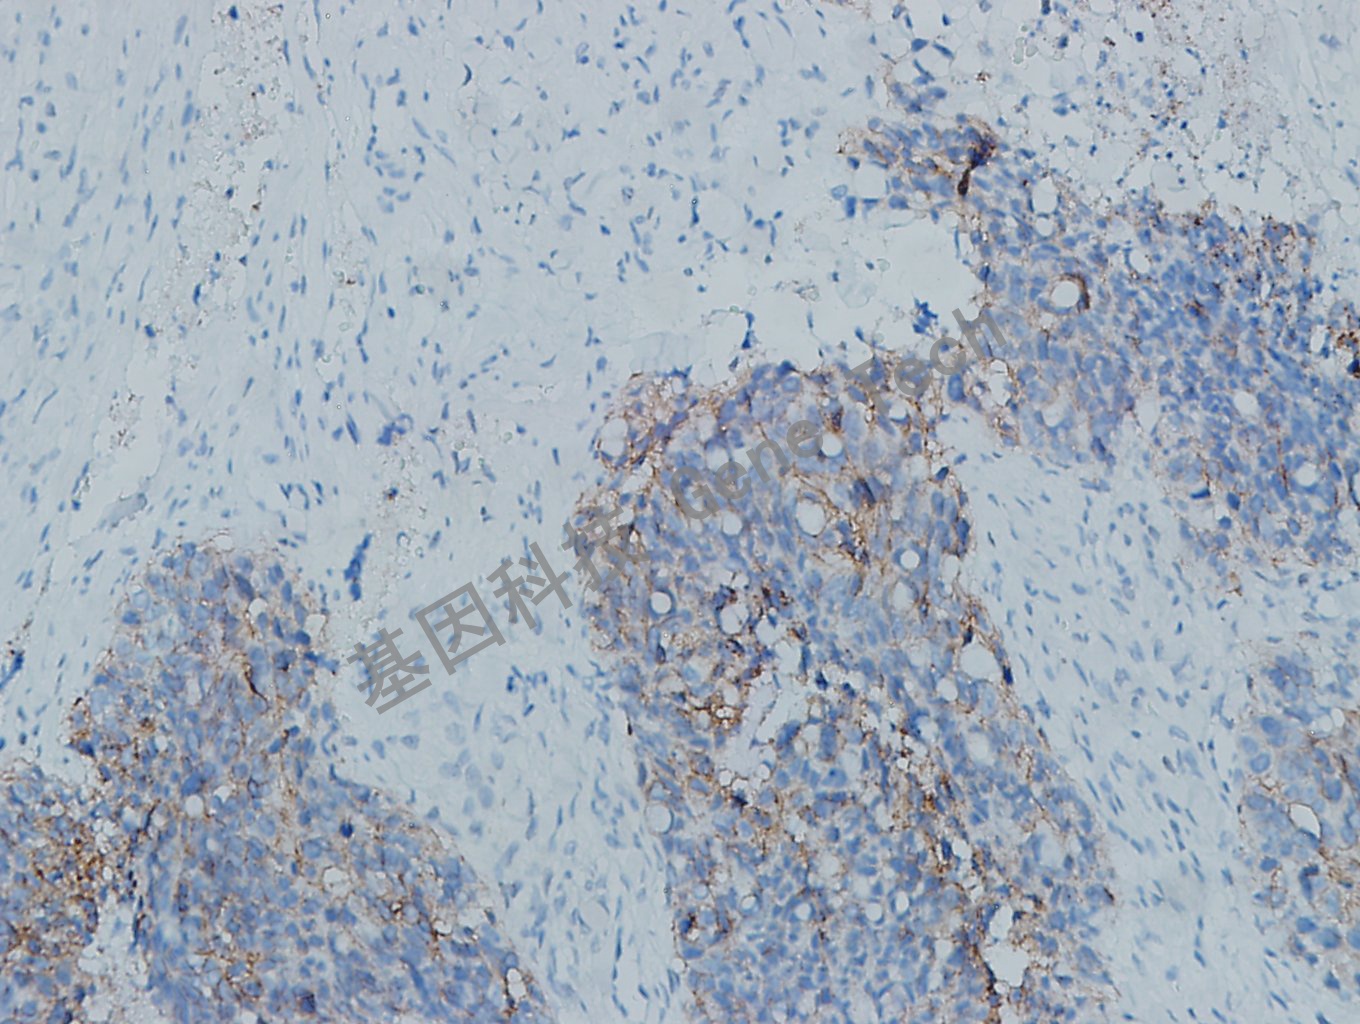

浆液性卵巢癌石蜡切片,用Claudin-3(GT2399)染色,细胞膜阳性,DAB显色。